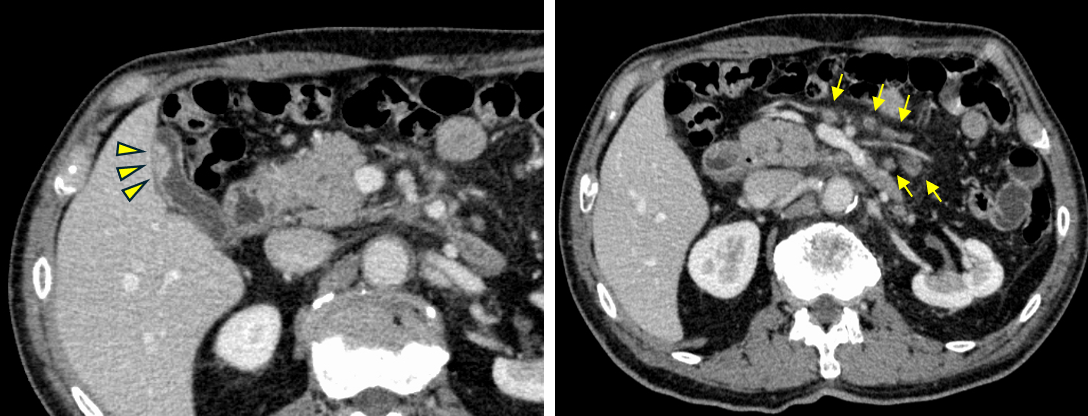

当院で行った造影CT検査では、肝内胆管の拡張の起始部に造影効果を伴う壁肥厚(黄色矢頭)を認めました。

そこでEUS-FNAによる精査を行いました。EUSでは胆管内に低エコー腫瘤を認め(左上)、この病変に対して穿刺を行いました。その結果、腺癌と診断されました。

造影CT検査では、胆嚢内に造影効果を伴う隆起性病変を認めました(左図)。また、腹腔内には複数のリンパ節腫大も認められました(右図)。

さらに詳しく調べるため、EUSを行いました。EUSでは胆嚢内の腫瘍性病変と腹腔内リンパ節腫大を確認したため、それぞれに対してEUS-FNAを行い、組織を採取しました。